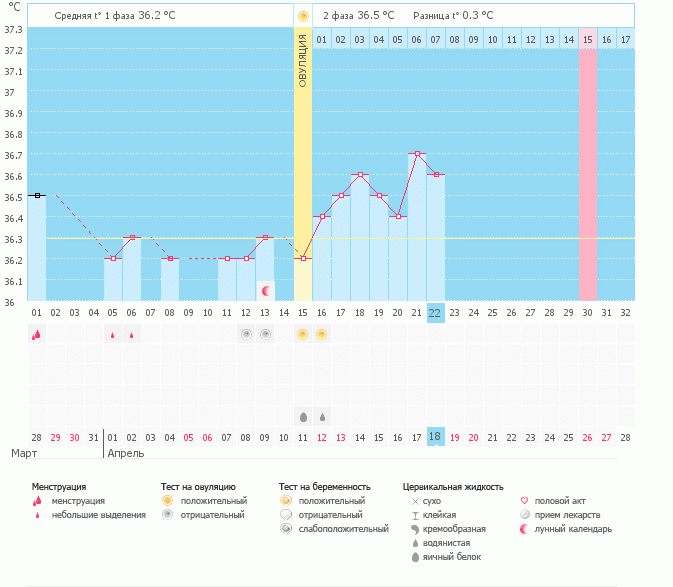

У меня только там труба осталась! Я аж там попрыгала от счастья  Но! Знаю свой организм, чувствую О как родную. Был ЯБ, были 2 гиперположительных теста на О, выделения сейчас как во второй фазе и график БТ ниже.

Но! Знаю свой организм, чувствую О как родную. Был ЯБ, были 2 гиперположительных теста на О, выделения сейчас как во второй фазе и график БТ ниже.

Я двести раз переспросила, может это ЖТ? А она НЕТ 100%. К слову, у этого узиста была в первый раз. График, фото ЛЯ: